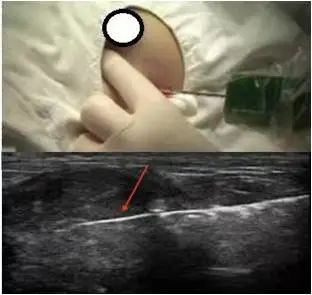

乳腺活检穿刺指的是发现乳腺肿块,通过穿刺取可疑组织进行病理检查,进一步明确诊断。病理检查是诊断乳腺癌最准确的一种方法。如果在做穿刺检查后发现有癌细胞或癌组织,就能够确诊患者乳腺的肿块是恶性的,也就是我们常说的乳腺癌。那么,穿刺活检怎么做?会导致肿瘤转移吗? 1.为什么做穿刺活检? 有人问,为什么触诊和专科影像学检查例如超声、钼靶、甚至乳腺MRI都高度怀疑乳腺癌,也不能明确诊断呢?影像学检查是医生借助机器的“眼睛”看肿块,而病理检查是在显微镜下观察组织,寻找肿瘤细胞。基本上所有的肿瘤都把病理结果作为诊断的金标准。 临床上也有一些朋友提出疑问:我不想做穿刺活检,可以直接手术切除吗?这就涉及到一个诊断性价比的问题。并不是所有的乳腺肿块都需要手术治疗,如果这样的病人直接手术,创伤大、花费高不说,患者自己也会经受手术的痛苦;如果手术中行冰冻切片检查,其准确率不如石蜡病理,可能需要再次进行麻醉和手术;对于一些肿瘤病人,可以通过穿刺活检结果判断是否行术前新辅助治疗,直接手术会造成贻误治疗时机。 目前,我国指南推荐使用的是空芯针穿刺活检(CNB),通常采用超声、钼靶或MRI等影像手段引导下进行操作。临床上以“超声引导下乳腺肿物穿刺活检”手段最多见。 2.穿刺活检会导致癌转移吗? 最近在网络上悄然出现流言,说肿物穿刺活检会导致肿瘤细胞转移,导致许多患者朋友对穿刺活检望而却步。实际上,其实,实际工作中因为穿刺导致转移的案例少之又少。 目前广泛采用的空心套管细针外面有一个保护鞘,就像圆珠笔的笔芯和笔杆一样,启动开关时,穿刺针就会刺入肿瘤而保护鞘仍然位于瘤外,取材结束后穿刺针又会缩回到保护鞘中,这样在穿刺针拔出的过程中就避免了癌细胞的外漏。同时,在超声引导下,可以有效避开大血管,最大程度降低肿瘤细胞进入循环的可能。 有研究显示,穿刺确实可能会发生及其少量的肿瘤细胞“掉落”,这些逃兵会被免疫系统攻击消失,并且极少的细胞数量基本上难以形成“针道转移”。即使出现肿瘤细胞种植,其倍增时间也需要数周至数月。如果能够在穿刺活检后的数周内进行手术切除,术后辅以放化疗、靶向治疗或免疫治疗,肿瘤扩散转移的风险也会被抵消。而且穿刺前,穿刺点和针道的路径,都会设计在切除手术的切口范围内,如果最终结果确诊了乳腺癌,在手术时就可以把穿刺点和针道一并切除,进一步让微乎其微的风险无“种植”之地。研究表明,穿刺活检造成扩散转移的风险低于千分之一,属于极低概率的罕见事件,几乎可以忽略不计。 穿刺活检是一项安全且有效的检查手段。所以,仅仅因为概率极低的事件而不愿意采取针刺活检,真的没有必要。 3.那么,穿刺活检是否可以通过其他无创手段替代呢? 就现阶段技术而言,穿刺活检仍然是不可或缺的检查手段,甚至被誉为术前“金标准”。影像学检查和血液学检查都可以辅助诊断肿瘤,但这些检查在面临复杂病情时往往无法确定肿瘤的性质,例如在乳腺癌诊断中,影像学往往只能提示恶性可能,此时还是需要穿刺病理确定肿块的良恶性。 我们要注意,穿刺尤其是细针穿刺所取组织样本有限,并不能完全反映肿块的整体情况,少数情况下还需要免疫组化染色等进一步病理手段来明确诊断。部分疾病里,也可以选择直接手术取材而不用穿刺。例如肺小结节往往直接进行手术切除,术后病理确诊,而无需术前穿刺。 穿刺活检前一定要关注凝血功能,如果服用抗凝药物需要遵医嘱提前停药,穿刺完成后要按压操作区域及时止血。常规的乳腺肿块穿刺不需要使用抗生素,如果是感染区域穿刺,需要遵医嘱进行抗生素的预防性使用。 一句话总结,乳房肿物穿刺活检术是一项微创、安全、结果可靠的确诊手段,对于可疑的乳房肿物,该出手时就出手。 作者:山西医科大学第一医院乳腺科 贾红燕